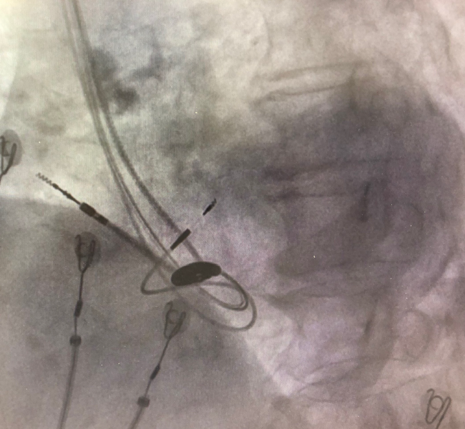

由于明确患者没有合适的靶静脉,薛玉梅主任果断更换手术策略,改行左束支起搏代替左室电极,电极精准放置于左束支区域,起搏图形呈典型左束支起搏,高低电压(1V及5V)达峰时间均为75ms,确定为选择性左束支起搏。起搏阈值仅为0.7V/0.4ms,效果良好;随后心房电极及右室除颤电极均顺利植入,参数良好,在连接好机器后,完美结束手术。

术后不同体位下影像

术中手术过程